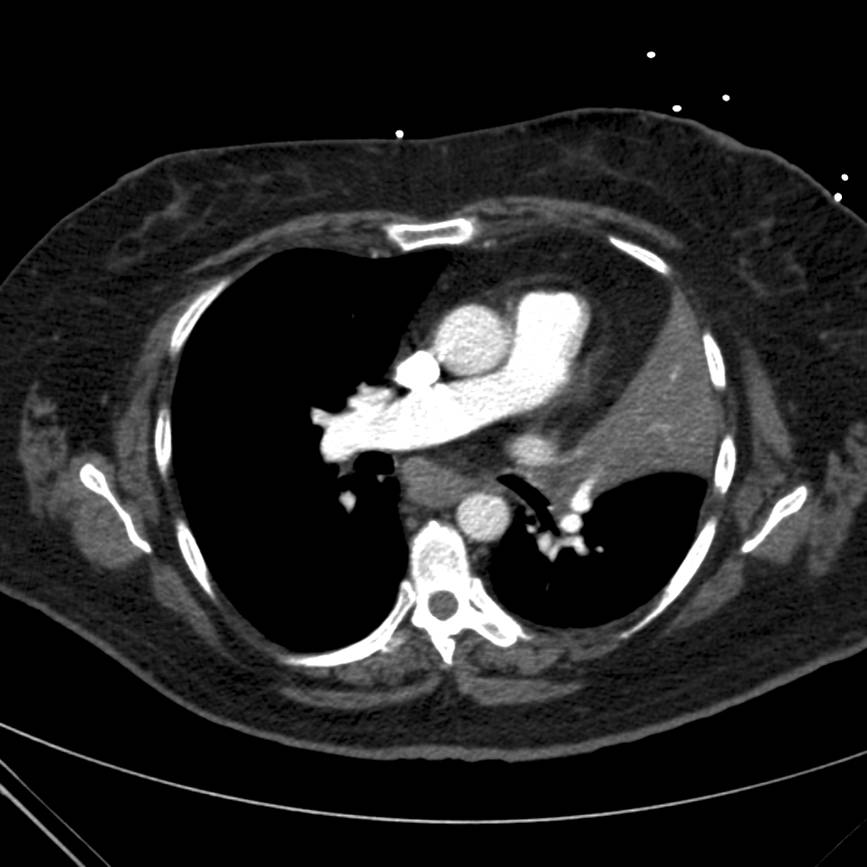

Subsequently the patient underwent computed tomography (CT) of the chest with pulmonary angiography. Two cuts are provided below (Figures 3 and 4).

Figure 3. Computed tomography image of the chest demonstrating consolidation of the left upper lobe.